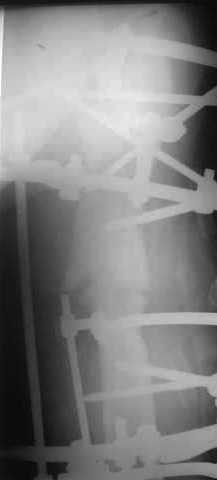

Вчера сделали рентгенограммы бедра нашему пациенту. Угловое смещение нам удалось исправить.

Сейчас проводим дистракцию (2 см).